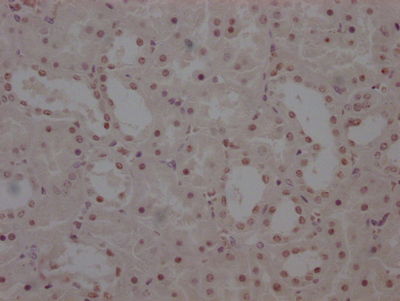

應用范圍:ELISA, IHC

Application Recommended Dilution IHC 1:20-1:200 -